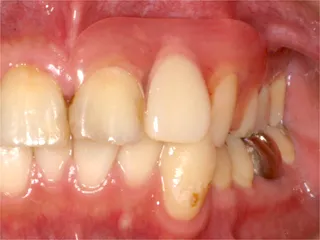

治療前

インプラントは第二の歯とも呼ばれ 顎の骨に金属製のネジを立てて 人工の歯を取付けます 当院では高い技術と経験で対応しています ■長所 ・しっかり噛むことができる ■短所 ・禁忌症がある ・高い インプラント・くわしく |